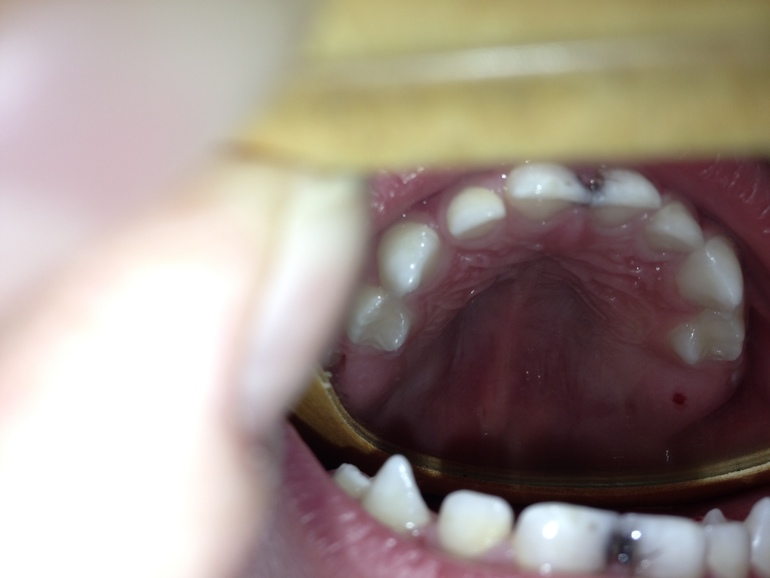

Алина, добрый вечер! вот фото с зеркалом, к сожалению это лучшее, что смогли сделать. низ изнутри так и не получился((( что касается изменения, вроде нет, хотя небольшое белое пятнышко наводит на мысль, что начинается еще один кариес(. и еще вопрос по фото - у него режутся последние жевательные, есть красное пятно - это не критично надеюсь? сосудик?  Заранее спасибо!!bbba34ed4545b4babe524b26b7a1abb6.jpgcff76e37a1eaac15884b45cf51e3561e.jpg925d9a5b0347a9820ea13ab19fb0c327.jpg7fd2df8acd6ded7a86d3a952b0d3c1d2.jpg

Здравствуйте.А на внутренней поверхности есть изменения? Сможете сделать фото через зеркало. чтобы была видна внутренняя поверхность?